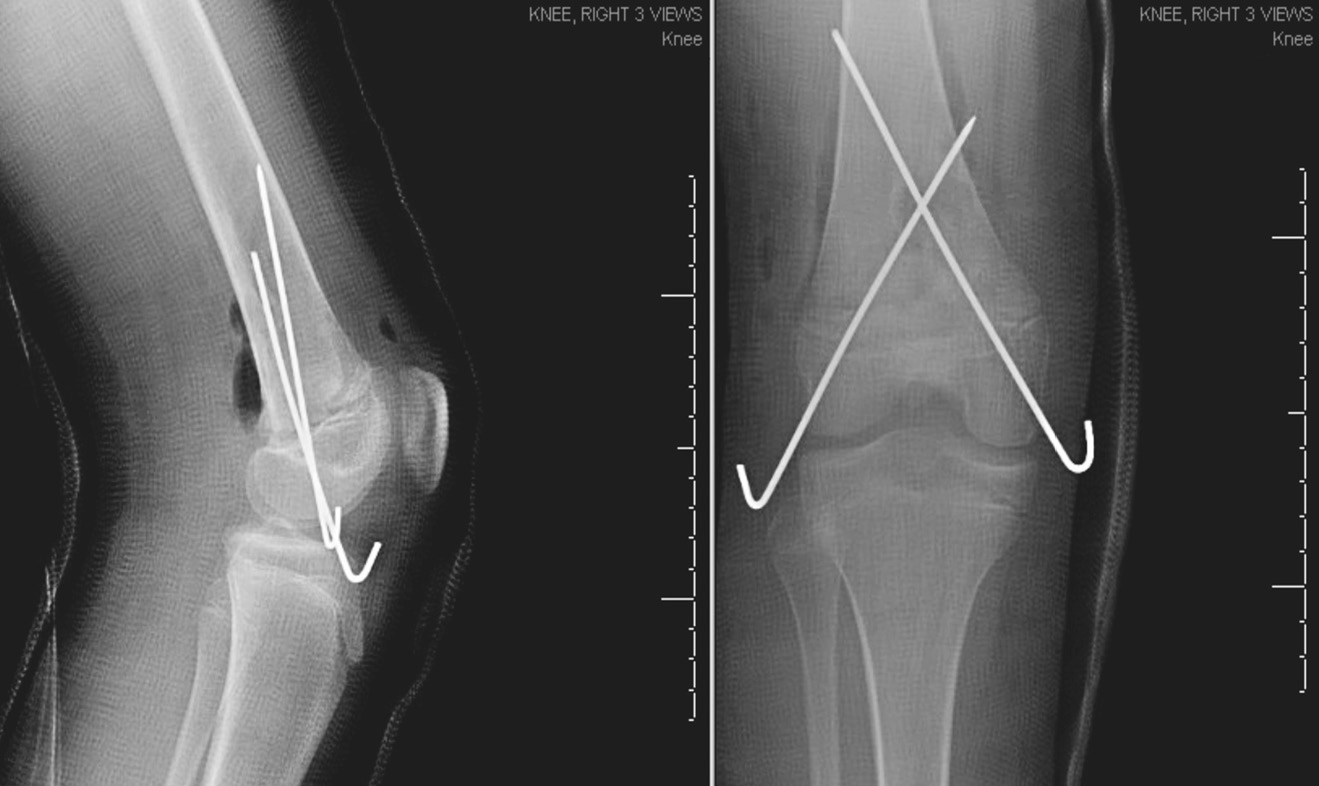

Рентген показал перелом дистального отдела правой бедренной кости с сильным смещением и повреждением зоны роста (рис. 2). При осмотре была выявлена колотая рана в задней части бедра, выстояние надколенника, рекурвация конечности и ее вынужденное сгибание в коленном суставе. Рот пациентки был относительно маленьким, но не было отмечено аномалий нёба или сколиоза. Периферическая чувствительность и разгибательная функция большого пальца стопы нарушены не были. Пульс на тыльной артерии стопы с двух сторон ощущался пальпаторно на 3+ и был подтвержден допплерографически. Лодыжечно-плечевой индекс правой и левой нижних конечностей составил 1,2 и 1,1 соответственно. Родители пациентки были уведомлены о возможном нарушении роста. Вакцинация против столбняка была проведена своевременно. Перед операцией был введен 1 г цефазолина внутривенно.

Рис. 2. Рентгенограмма правого коленного сустава в боковой проекции, показывающая перелом дистального отдела бедренной кости Салтер – Харриса 2-го типа со смещением

Был выполнен заднебоковой разрез в области дистального отдела правого бедра. После тщательного промывания 9 л изотонического раствора натрия хлорида была высвобождена ущемленная надкостница и выполнена репозиция перелома. Перелом зафиксирован в удовлетворительном положении с помощью перекрестной установки спиц через дистальный эпифиз бедренной кости. Нормальное кровоснабжение было подтверждено допплерографически, и рана ушита. Пациентке был наложен длинный гипс без возможности опоры на ногу. На послеоперационных рентгеновских снимках видна удовлетворительная репозиция дистальной части бедра (рис. 3). Поскольку пациентка была иногородней и ее дом находился в 3 часах езды от больницы, врачи рекомендовали ей остаться в больнице на 2 дня во избежание развития компартмент-синдрома или нейрососудистых нарушений и для завершения 48-часового введения цефазолина внутривенно. Затем пациентка была выписана домой. Девочка оставалась в гипсе без опоры на ногу в течение 4 нед. Спицы были удалены через 6 нед. По истечении 6 мес. пациентка прошла контрольное обследование, которое показало, что она не испытывает затруднений в движении. Восстановление прошло успешно, и ребенок снова смог посещать уроки физкультуры. На заключительных рентгенологических снимках через 6 мес. репозиция сохранялась. Пациентка наблюдалась в течение 2 лет, при этом у нее не было отмечено угловой деформации конечности или различия в длине ног.

Рис. 3. Рентгенограмма правого коленного сустава в переднезадней и боковой проекциях после открытой репозиции и внутренней фиксации. Видна нормальная репозиция с фиксацией двумя спицами, перекрестно установленными через эпифиз